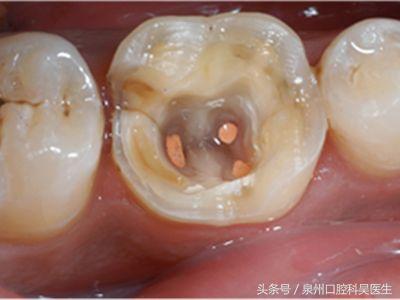

简单来说,根管治疗就是口腔医生把有病变的牙齿打开,然后将牙齿里面发炎、龋坏、坏死的牙髓组织用专业器械清除干净,并把牙髓腔内进行(包含牙髓腔壁)消毒,清洁,最后再用牙胶等物把牙髓腔紧密地封填起来。

一般情况下,根管治疗适用于牙髓炎,牙髓坏死,以及各种类型的根尖周炎,也包括由于龋齿、隐裂、过度消耗、穿髓等引起的牙髓炎及牙髓坏死致不能保留活髓的情况。